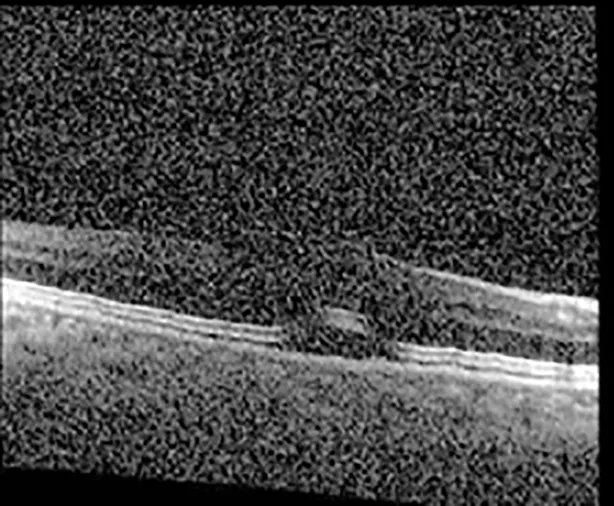

The patient began treatment with oral pemigatinib daily and was followed up for an ophthalmic examination during the second treatment cycle approximately 5 weeks into the treatment process. The patient had at this stage received 28 doses of 13.5 mg per day, which was administered in cycles of 14 on-days and 7 off-days, and had no visual or ophthalmic complaints. The non-corrected VA was OD 20/30 + 1 and OS 20/20. The OCT examinations revealed subfoveal SRF bilaterally. The fundus examination was otherwise unremarkable outside the patient’s prior documented peripheral drusen. Repeat autofluorescence was overall unchanged, though a slight hypofluorescent ring may be visualized in Figure 2. The current pemigatinib protocol recommendation for asymptomatic patients suggests no dose modification; however, with worsening presentation or positive symptoms, it is recommended to withhold pemigatinib. After discussion with the patient’s oncologist, it was decided to continue the medication at this time. Serial monitoring of the patient’s symptoms, vision, and SRF were conducted on specific days during active treatment cycles and days off-cycle to monitor the SRF. Subsequent evaluations demonstrated complete resolution of SRF while off-cycle, and asymptomatic re-accumulation of fluid while on-cycle with varying levels of VA. (Table 1) As we see demonstrated in the table below, in the later stages of the active cycles, such as day 13 of 14 of cycle 2, day 13 of 14 of cycle 3, day 13 of 14 of cycle 4, and day 14 of 14 on cycle 5, the patient’s VA showed no correlative changes based on the presence of SRF. The fluctuations in the patient’s VA certainly occurred, but were likely to be secondary to surface changes, as certain off-cycle days actually presented with lower acuities than days when the SRF was present on OCT examination.

| Cycle, day, on/off | VA OD; OS | CMT OD; OS | OCT OD | OCT OS |

| Cycle 5, day 6, off | 20/40+2; 20/30−2 | 276; 278 | ![]() | ![]() |

Highlights the visual acuity, central macular thickness, and the physical OCT of the macula for this patient in both the right and left eyes during various stages of the patient's chemotherapy treatment cycle.